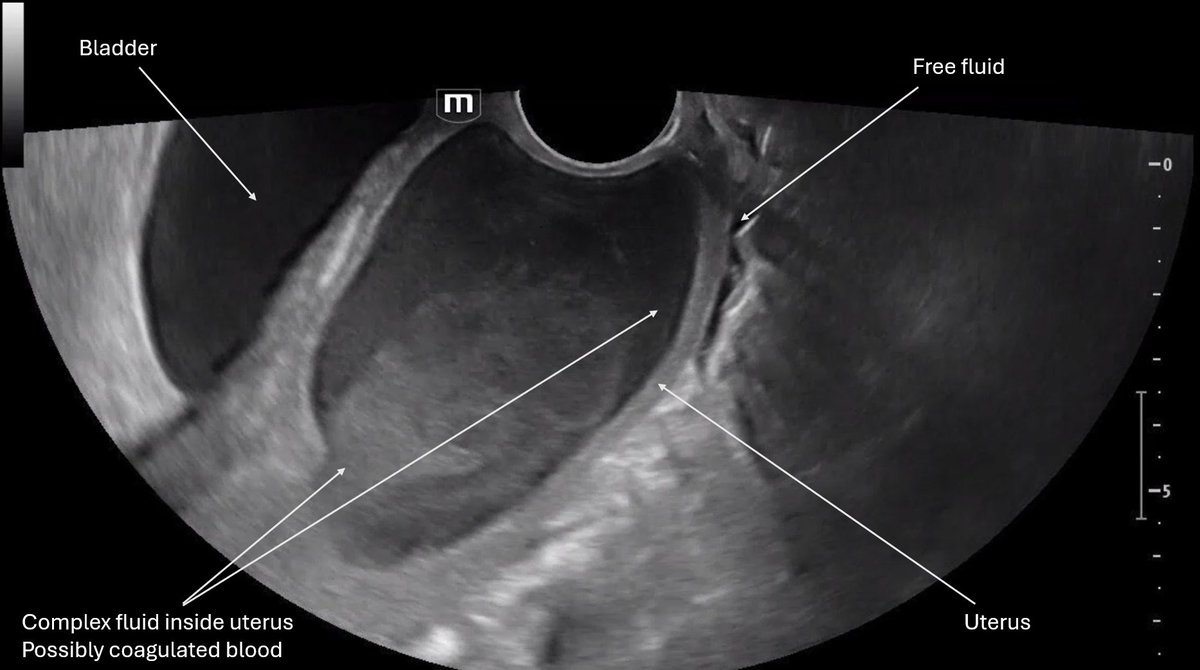

Patient is a 34 year-old F with G3P0 at 6 weeks gestation by LMP presents with LLQ pain and vaginal bleeding.